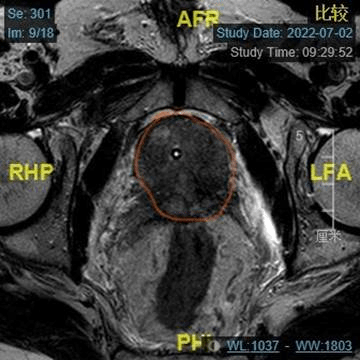

年近7旬的杨大爷,3个月前在当地医院发现自己患前列腺癌后,每天心事重重,失眠,家属看到杨大爷每天这种状态也心急如焚,在多方了解下找到ac米兰官网中文网站一院泌尿外科王春阳教授寻求治疗。住院后完善相关检查,TPSA>100ng/mL,前列腺MRI考虑前列腺癌,侵及双侧精囊,前列腺大小约37g,结合病史及检查,杨大爷前列腺癌已是局部晚期,需即刻行手术治疗,但手术风险高,效果差,建议先行新辅助内分泌治疗,再行手术治疗。

出院后杨大爷定期使用新辅助内分泌治疗,3个月后再次到我院就诊,复查TPSA及前列腺MRI,TPSA降至0.06ng/mL,游离PSA/总PSA为0.32,前列腺MRI提示病变与3个月前比较,病变范围缩小,前列腺大小约18g,与3个月前相比明显缩小。王春阳主任认为杨大爷现在行手术治疗,术后效果能达到预期。